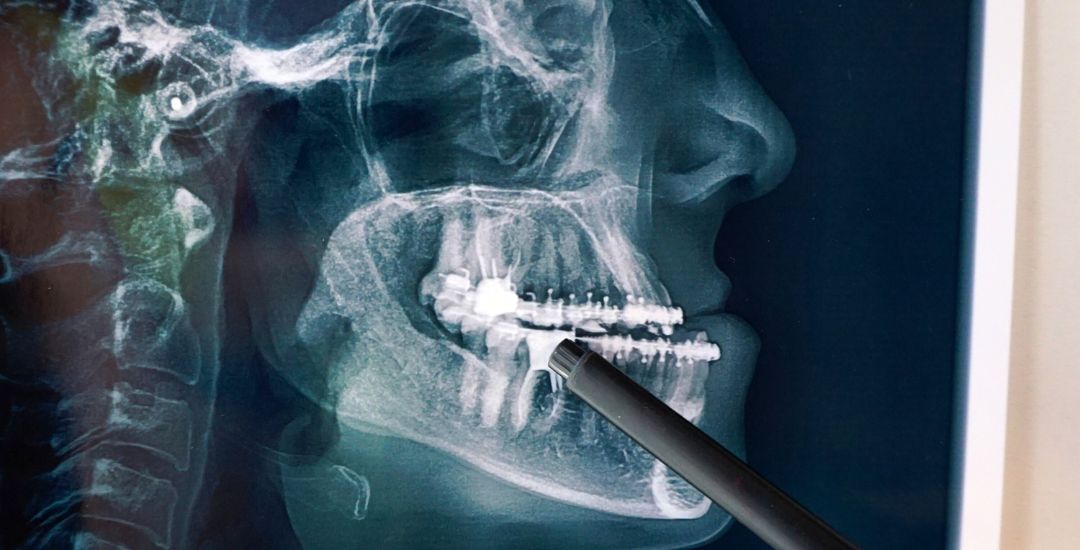

All-on-4 ve All-on-6 İmplant Sistemleri

Antalya’da All-on-4 ve All-on-6 implant tedavileriyle eksiksiz bir gülüş kazanın. Dr. Onur Ademhan ve Perla Dental Clinics, kalıcı estetik çözümler sunar.